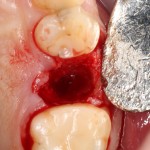

Для удаления зубов мы используем прямой элеватор и тонкие «корневые» щипцы-байонеты. Сама процедура удаления занимает около 10 минут:

Давайте внимательно посмотрим на состояние лунок центральных резцов после удаления:

Приемлемый фенотип (сочетание толщины и ширины участка жевательной десны) — это, конечно, приятно. Но гораздо важнее сосредоточиться на рисках, их на этот момент два:

— травматическое повреждение слизистой, вызванное удаление зубов связано с тем, что при хроническом воспалении слизистая оболочка теряет эластичность, поэтому легко рвётся. Такая ситуация создаёт серьёзную угрозу эстетическому результату лечения, в зависимости от того, насколько быстро десна придёт в норму.

— как и предполагалось после КЛКТ, утрата костной стенки привела к тому, что десна провалилась в просвет лунки левого центрального резца. Это еще больше усугубляет клиническую ситуацию.